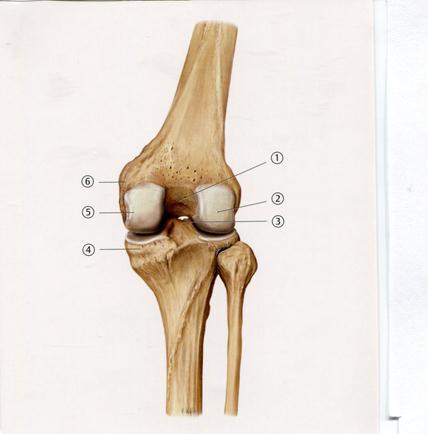

А.Алдыңғы төмпешік

В. Артқы төмпешік

42. Төменде көрсетілген суреттегі белгіленген №5 анатомиялық құрылымды атаңыз.

В. Айдаршықаралық қырат